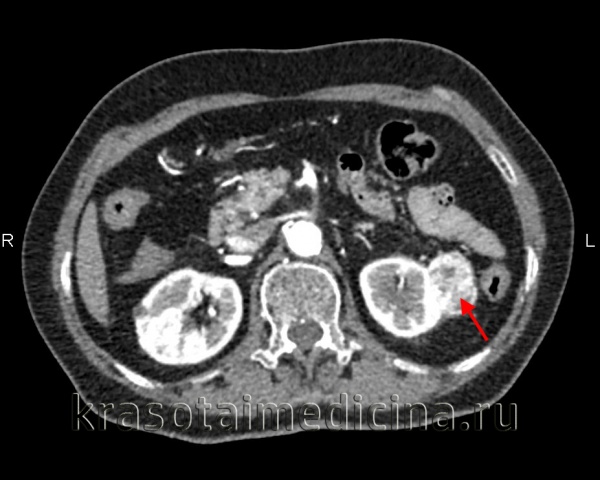

КТ органов брюшной полости и забрюшинного пространства. Аденокарцинома левой почки с типичным накоплением и вымыванием контраста

а - Результаты внутривенной урографии при карциноме почки. В левой почке видна опухоль (указана стрелкой), деформирующая почечные чашки.

б - Артериограмма почки (поздняя артериальная фаза). Видна область гиперваскуляризации, соответствующая большой опухоли, занимающей две трети почки.